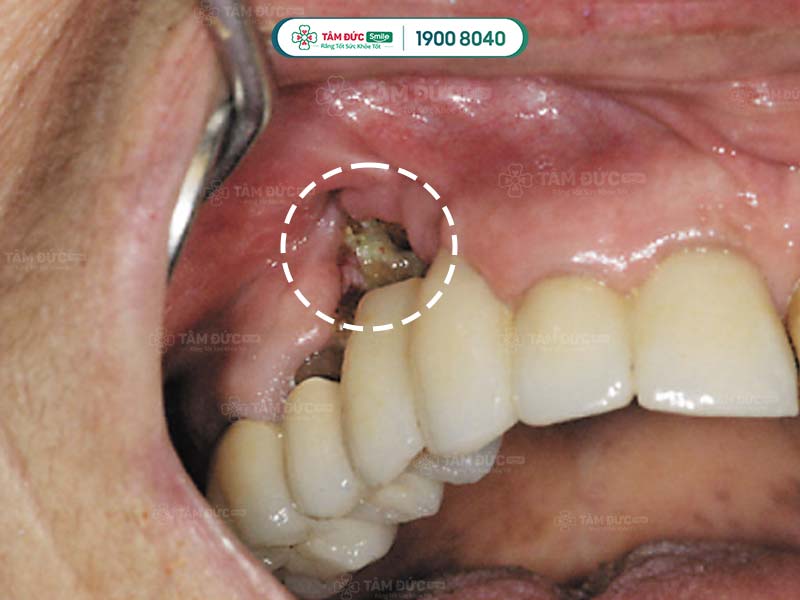

2.2. Sâu răng gây viêm xương hàm

Răng sâu không được xử lý kịp thời có thể dẫn tới tình trạng viêm tủy, viêm mô mềm. Đây chính là môi trường lý tưởng cho sự phát triển của vi khuẩn, từ đó dẫn tới viêm xương hàm.

Sâu răng gây viêm xương hàm